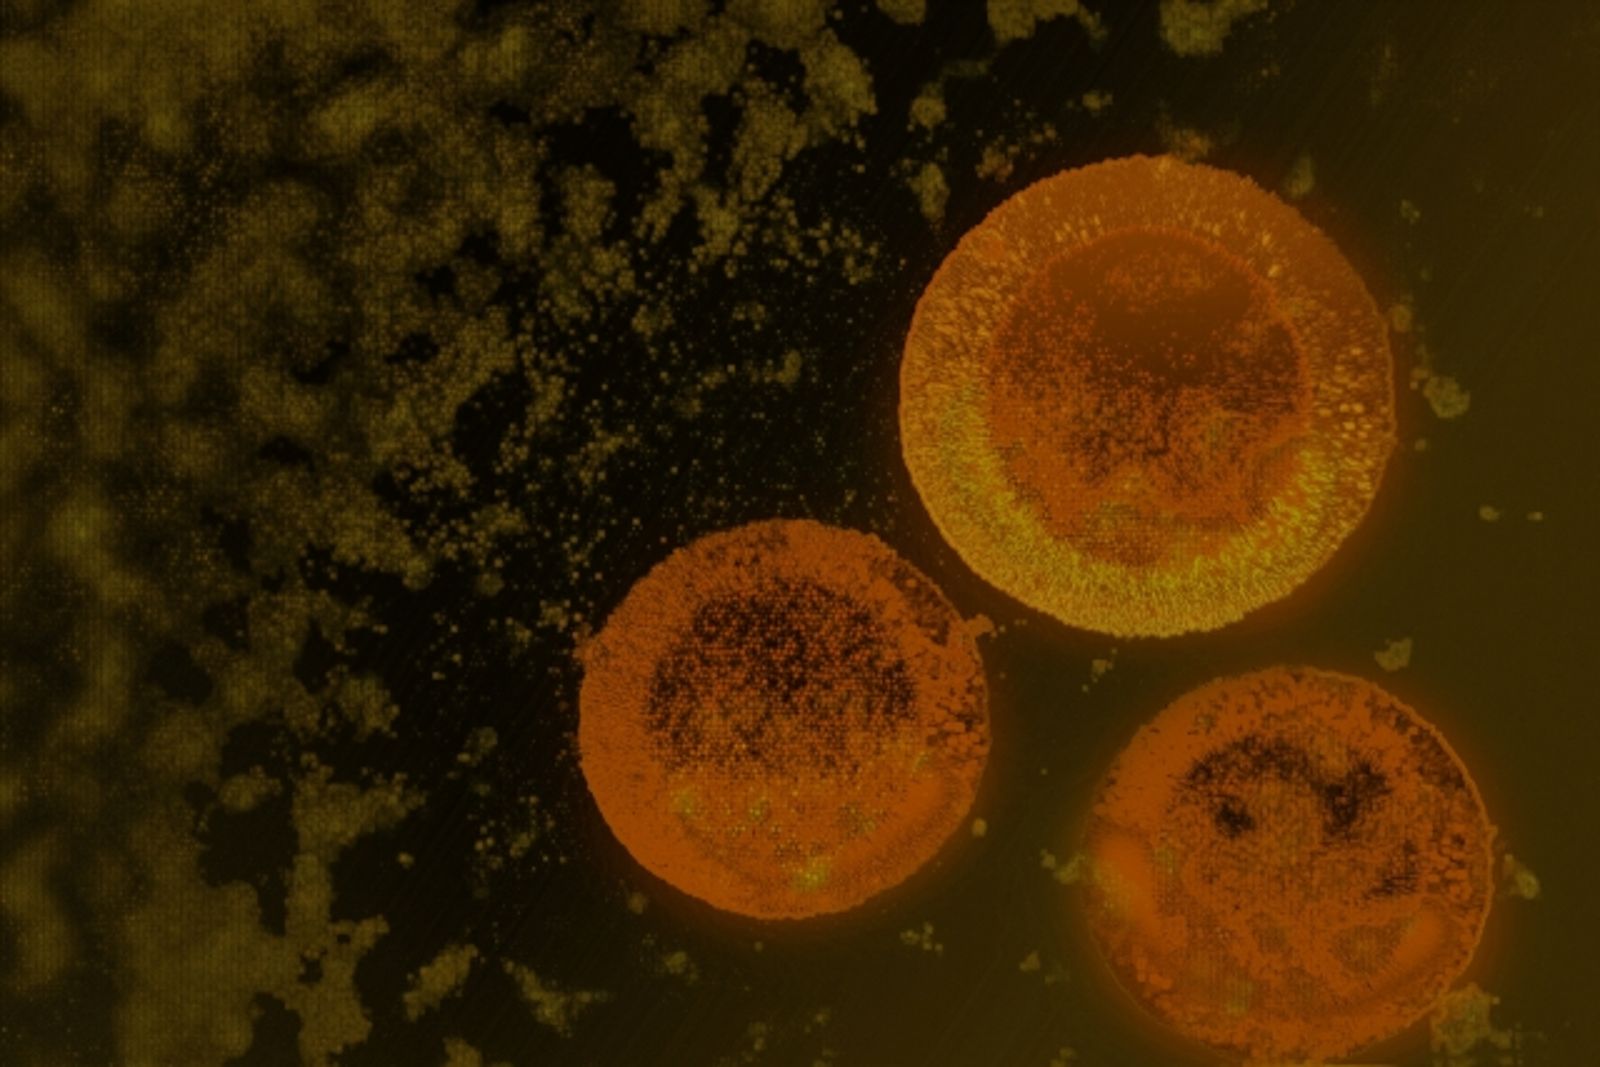

PFAS常應用於塑膠製品、紡織品以及不沾鍋塗層,一旦進入體內就難以被排出,過去曾有報告指出,該物質可能增加致癌、不孕症風險,因此被列為體內致癌有毒化學物質;然而根據Daily Mail報導,劍橋大學日前進行一項研究,在人類腸道中採集38種細菌樣本,並植入實驗鼠體內,結果發現,體內沒有細菌的老鼠其PFAS物質較含有細菌的老鼠高出74%。

劍橋大學毒理學家Kiran Patil以細菌對PFAS中的一類致癌物全氟壬酸(PFNA)及二類致癌物全氟辛酸(PFOA)含量影響進行研究,其中有9種細菌分別將PFNA含量降低25%至74%、PFOA含量降低23%至58%,又以內臟臭桿菌(Odoribacter splanchnicus)減少PFAS物質效果最為顯著。

專家指出,內臟臭桿菌能產生短鏈脂肪酸丁酸,從而促進新陳代謝和免疫功能,又因PFAS會以團塊的形式附著在細菌上,細菌再經由糞便排出體外,降低體內致癌物質含量。雖然目前還沒有找到完全消滅致癌物質的方法,不過專家認為這些細菌為人類提供了清除有害物質的可能性,將嘗試開發出以這些細菌為主的益生菌補充劑,來增加腸道中有益細菌的含量。